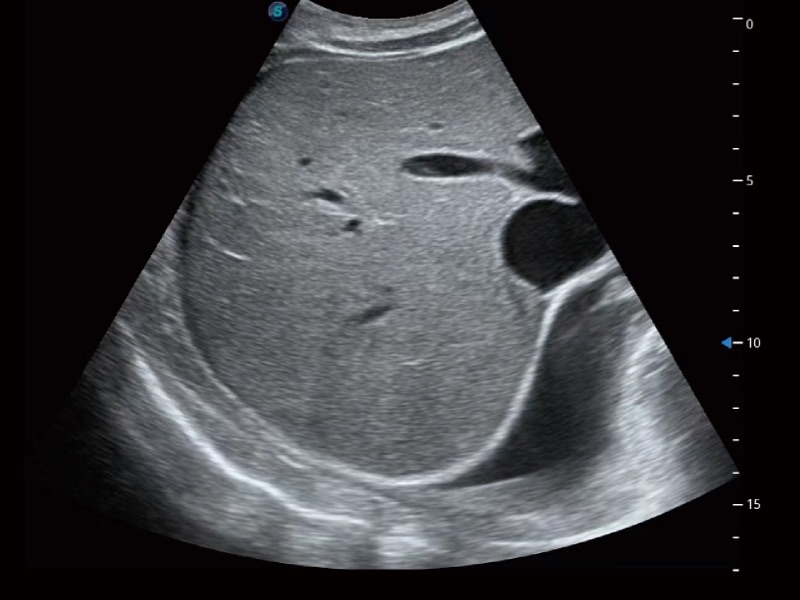

• 腹部应用

超声检查得益于实时性、经济性、便捷性,目前广泛的应用于临床工作中,超声检查设备已成为帮助临床医生轻松地完成诊断工作的好伙伴。P20 Plus集成了一整套包含了腹部、心血管、小器官、妇产科等全面临床应用功能,轻松应对各种临床问题。